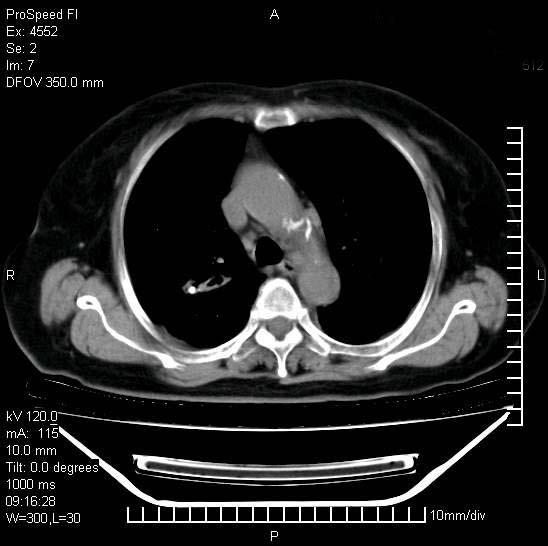

标题: CT15528:女性,79岁,近几日晚上高热,39度,仍咳少量血 [打印本页]

标题: CT15528:女性,79岁,近几日晚上高热,39度,仍咳少量血

十几年前曾患肺结核,一周前突咳血约100ml,中性粒细胞稍高,诊断两上肺陈旧结核,下肺炎症,给予抗炎治疗,近几日晚上高热,39度,仍咳少量血,4天前ct及今天ct上传。

今天ct

短短几天内,病变范围明显增多扩大,以左侧明显,而且双侧出现胸水,还是考虑感染.

短短几天内,病变范围明显增多扩大,以左侧明显,而且双侧出现胸水,我更多考虑左侧中心性肺癌并并阻塞性不张及肺炎,炎症变化也太快了!

无论是肿瘤还是炎症4天的时间都发展够快的,并且还在治疗中,如果说是左肺癌那么右肺的病变不好解释,本人更加倾向于炎症,左肺舌叶支气管被痰栓或血凝块堵塞,造成阻塞性肺炎。

1)两肺结核并感染。2)不排除左肺上叶中央型肺癌并阻塞性肺炎、肺不张可能;建议行纤支镜检查。3)右肺门及纵隔淋巴结肿大。4)双侧胸腔积液。

陈旧性肺结核及左下肺不张,咯血后肺部感染,双胸腔积液,高热可能与痰液引流不畅有关。